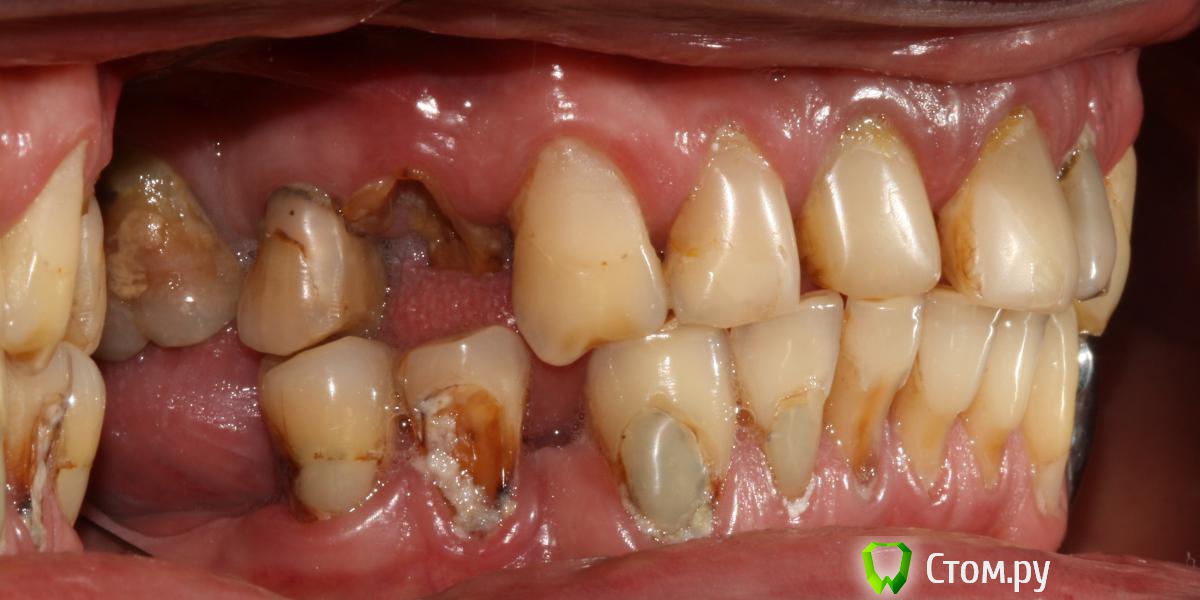

Привет всем! уважаемые Гуру помогите с планированием реабилитации данного пациента. Основная жалоба, не хочет носить съемный протез (пришел из другой клиники, где рекомендовали только съемное протезирование).

Провели обследование. Ортопед планирует оставить вверху 6 фронтальных зубов (возможно резцы пойдут на удаление), внизу только клыки. Далее последует удаление несостоятельных зубов + иммедиат протезы, продолжение реабилитации.

п.с. ДА, С ГИГИЕНОЙ ПОКА ЗАСАДА!!!)

С такой гигиеной не стал бы брать.

Если гигиенические навыки не изменятся - не берите этого пациента. (абсолютно согласен с Антоном)

Да и по уровню гигиены и состоянию зубных рядов можно судить о сознательности пациента, а она УХ как нужна при таких реконструктивных вмешательствах!

пациент уже проходит лечение у пародонтолога, планируется контроль гигиены на этапах протезирования (график посещений составляет пародонтолог)